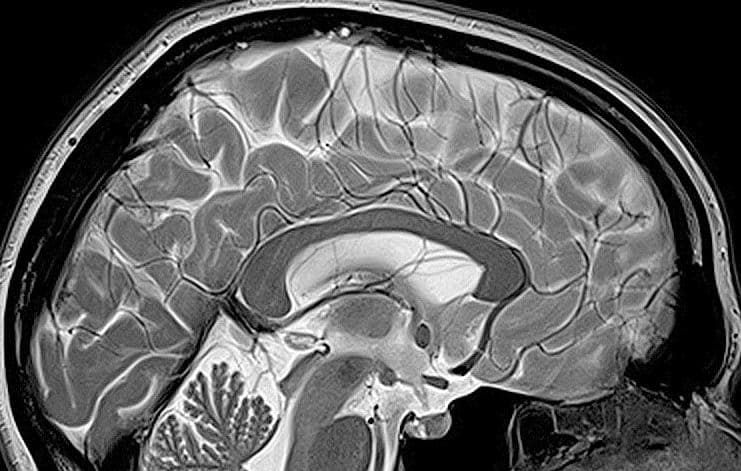

Une étude japonaise récente de 2025, menée par le professeur Akemi Tomoda à l’université de Fukui, apporte des réponses à ce sujet. En s’appuyant sur des méthodes avancées d’imagerie cérébrale, l’équipe montre que la négligence laisse des traces dans des zones clés du cerveau, essentielles aux mouvements, à la gestion des émotions et aux fonctions cognitives. Ces données permettent à la fois de mieux comprendre les conséquences invisibles de la négligence et de réfléchir à de nouveaux modes de détection et de prise en charge pour mieux soutenir les enfants concernés.

Les chercheurs ont utilisé l’imagerie par tenseur de diffusion (ITD), une méthode d’imagerie cérébrale avancée. Cette approche permet de visualiser la microstructure de la substance blanche, c’est-à-dire les fibres qui relient différentes zones du cerveau. Elle identifie les altérations fines qui ne se voient pas sur les images classiques comme l’IRM standard. La technique révèle comment les signaux passent d’une région à l’autre, ce qui informe sur la qualité des connexions neuronales chez chaque enfant. La détection de modifications subtiles apporte une valeur ajoutée : elle met en lumière les impacts cachés de la négligence, parfois longtemps avant que des troubles comportementaux ou émotionnels n’apparaissent. Utiliser l’ITD dans ce contexte permet aux médecins et aux chercheurs d’aller au-delà de l’observation des symptômes pour saisir des modifications précoces et objectives.

L’échantillon de l’étude compte 21 enfants victimes de négligence et 106 enfants au développement typique. Cette proportion offre une comparaison solide et renforce la pertinence des résultats. Contrairement à d’autres recherches qui se cantonnent à la surface ou qui ciblent une zone spécifique du cerveau, cette étude a choisi de procéder à une analyse du cerveau complet. Ce choix méthodologique élargit la perspective scientifique et évite de passer à côté d’altérations moins connues ou inattendues. Les enfants étudiés ne présentaient pas d’autres formes de maltraitance connues, ce qui élimine de nombreux biais et confère aux différences constatées une spécificité rare. Avec cette base, il devient possible de relier les anomalies observées à la négligence seule, et non à un ensemble de facteurs confondants. Ce travail pose ainsi les fondations d’une évaluation nouvelle du risque associé à la négligence infantile, soutenue par des données objectives et reproductibles.